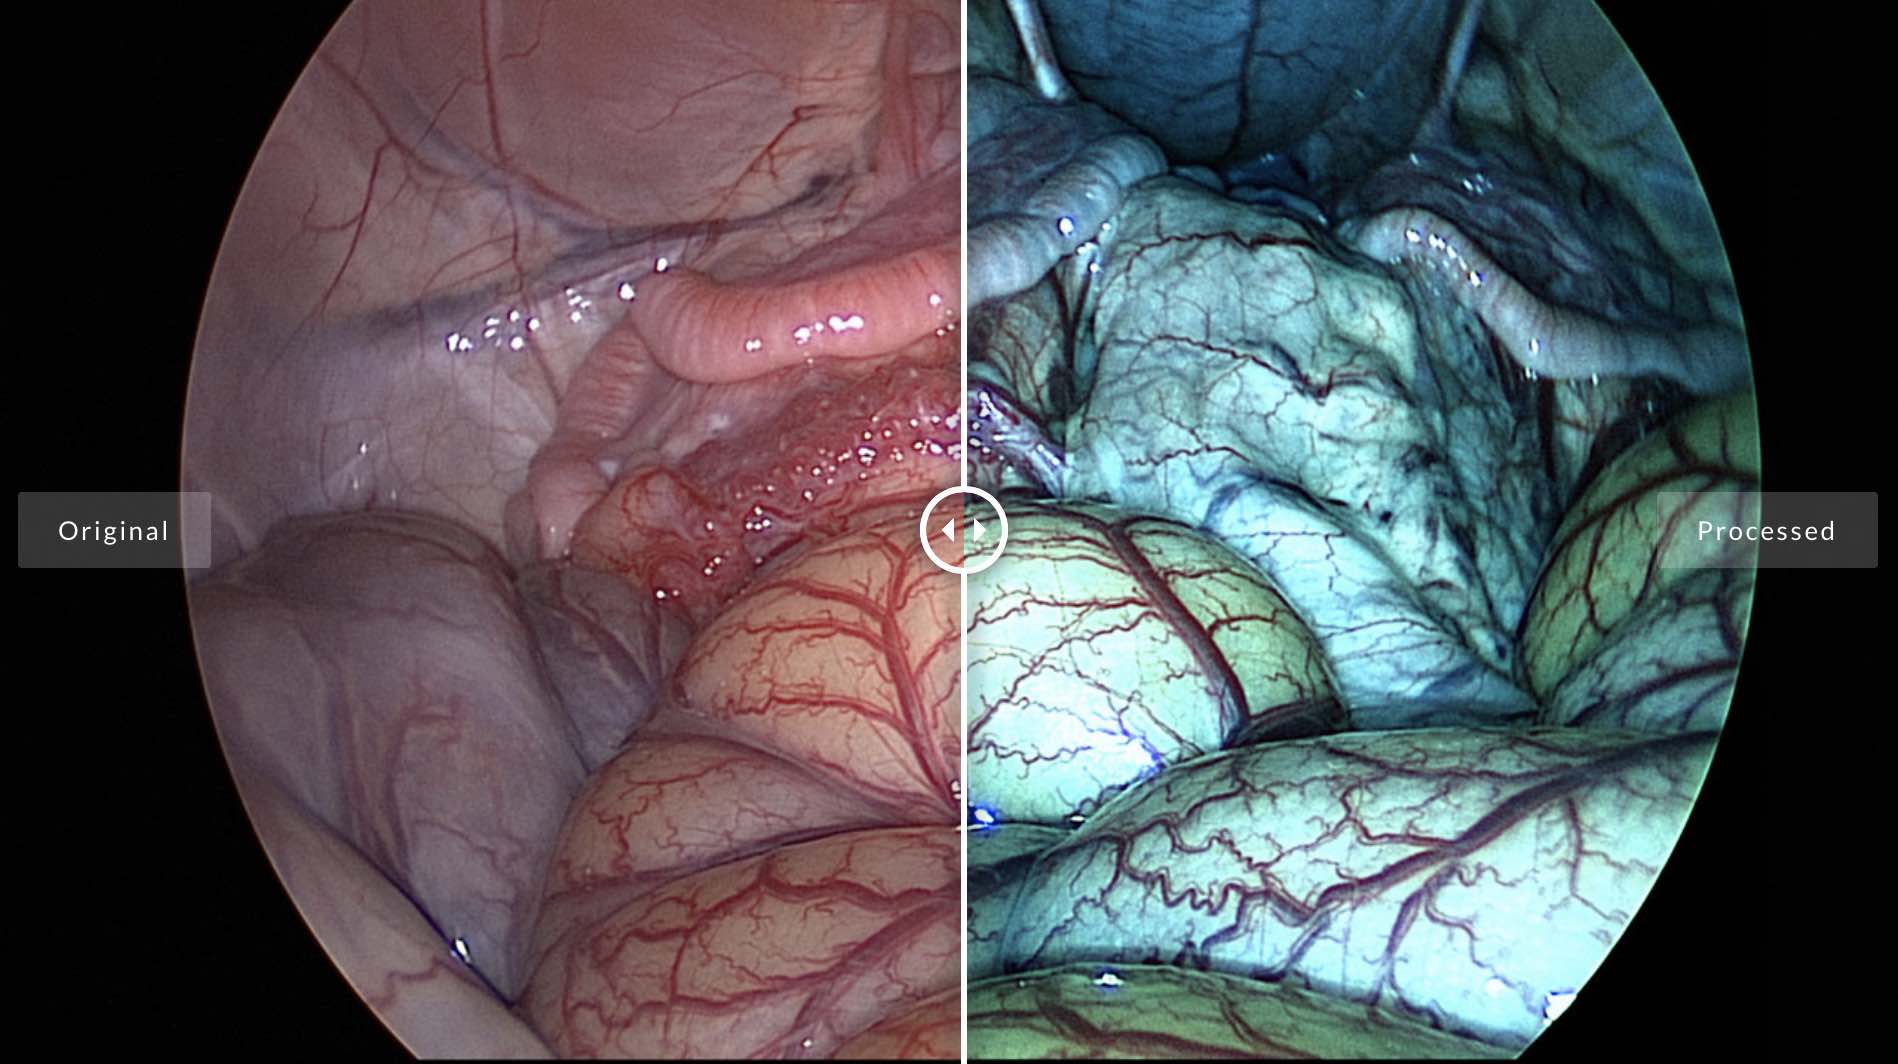

Founded in 2013, Coimbra startup Perceive3D has raised $2.8 million to develop intelligent video technology for surgical procedures involving endoscopy. The startup’s algorithms enhance imaging in the operating room by brightening and sharpening images, correcting for the fish-eye effect of the equipment, and mapping contrasting colors to anatomic elements.

Founded in 2013, Coimbra startup Perceive3D has raised $2.8 million to develop intelligent video technology for surgical procedures involving endoscopy. The startup’s algorithms enhance imaging in the operating room by brightening and sharpening images, correcting for the fish-eye effect of the equipment, and mapping contrasting colors to anatomic elements.

Perceive3D also offers Augmented Reality (AR) tools on the back of its image processing capabilities that assist surgeons with joint and knee surgery by accurately visualizing patient anatomy and overlaying the image with AR pointers. The company’s AR technology has been successfully tested on a cadaver, January this year, and will be available to surgeons by 2020 according to the startup’s CEO. Sounds similar to the sort of surgical imaging technology we saw on display at Stanford this spring.